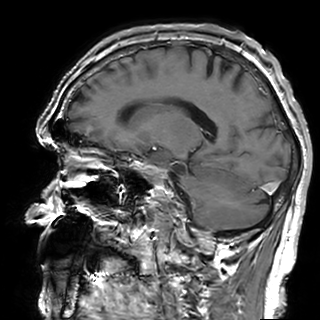

Refer to captionRefer to caption𝐱PCsubscript𝐱PC\mathbf{x}_{\mathrm{PC}}bold_x start_POSTSUBSCRIPT roman_PC end_POSTSUBSCRIPTRefer to captionRefer to caption𝐱LDsubscript𝐱LD\mathbf{x}_{\mathrm{LD}}bold_x start_POSTSUBSCRIPT roman_LD end_POSTSUBSCRIPTRefer to captionRefer to caption𝐱SDsubscript𝐱SD\mathbf{x}_{\mathrm{SD}}bold_x start_POSTSUBSCRIPT roman_SD end_POSTSUBSCRIPTRefer to captionRefer to captionAm-3D [14]Refer to captionRefer to captionPa-2.5D [8]Refer to captionRefer to caption𝐱^SDsubscript^𝐱SD\hat{\mathbf{x}}_{\mathrm{SD}}over^ start_ARG bold_x end_ARG start_POSTSUBSCRIPT roman_SD end_POSTSUBSCRIPT (ours)Refer to captionRefer to caption𝐱PCsubscript𝐱PC\mathbf{x}_{\mathrm{PC}}bold_x start_POSTSUBSCRIPT roman_PC end_POSTSUBSCRIPTRefer to captionRefer to caption𝐱LDsubscript𝐱LD\mathbf{x}_{\mathrm{LD}}bold_x start_POSTSUBSCRIPT roman_LD end_POSTSUBSCRIPTRefer to captionRefer to caption𝐱SDsubscript𝐱SD\mathbf{x}_{\mathrm{SD}}bold_x start_POSTSUBSCRIPT roman_SD end_POSTSUBSCRIPTRefer to captionRefer to captionAm-3D [14]Refer to captionRefer to captionPa-2.5D [8]Refer to captionRefer to caption𝐱^SDsubscript^𝐱SD\hat{\mathbf{x}}_{\mathrm{SD}}over^ start_ARG bold_x end_ARG start_POSTSUBSCRIPT roman_SD end_POSTSUBSCRIPT (ours)Refer to captionRefer to caption𝐱PCsubscript𝐱PC\mathbf{x}_{\mathrm{PC}}bold_x start_POSTSUBSCRIPT roman_PC end_POSTSUBSCRIPTRefer to captionRefer to caption𝐱LDsubscript𝐱LD\mathbf{x}_{\mathrm{LD}}bold_x start_POSTSUBSCRIPT roman_LD end_POSTSUBSCRIPTRefer to captionRefer to caption𝐱SDsubscript𝐱SD\mathbf{x}_{\mathrm{SD}}bold_x start_POSTSUBSCRIPT roman_SD end_POSTSUBSCRIPTRefer to captionRefer to captionAm-3D [14]Refer to captionRefer to captionPa-2.5D [8]Refer to captionRefer to caption𝐱^SDsubscript^𝐱SD\hat{\mathbf{x}}_{\mathrm{SD}}over^ start_ARG bold_x end_ARG start_POSTSUBSCRIPT roman_SD end_POSTSUBSCRIPT (ours)Refer to captionRefer to caption𝐱PCsubscript𝐱PC\mathbf{x}_{\mathrm{PC}}bold_x start_POSTSUBSCRIPT roman_PC end_POSTSUBSCRIPTRefer to captionRefer to caption𝐱LDsubscript𝐱LD\mathbf{x}_{\mathrm{LD}}bold_x start_POSTSUBSCRIPT roman_LD end_POSTSUBSCRIPTRefer to captionRefer to caption𝐱SDsubscript𝐱SD\mathbf{x}_{\mathrm{SD}}bold_x start_POSTSUBSCRIPT roman_SD end_POSTSUBSCRIPTRefer to captionRefer to captionAm-3D [14]Refer to captionRefer to captionPa-2.5D [8]Refer to captionRefer to caption𝐱^SDsubscript^𝐱SD\hat{\mathbf{x}}_{\mathrm{SD}}over^ start_ARG bold_x end_ARG start_POSTSUBSCRIPT roman_SD end_POSTSUBSCRIPT (ours)Refer to captionRefer to caption𝐱PCsubscript𝐱PC\mathbf{x}_{\mathrm{PC}}bold_x start_POSTSUBSCRIPT roman_PC end_POSTSUBSCRIPTRefer to captionRefer to caption𝐱LDsubscript𝐱LD\mathbf{x}_{\mathrm{LD}}bold_x start_POSTSUBSCRIPT roman_LD end_POSTSUBSCRIPTRefer to captionRefer to caption𝐱SDsubscript𝐱SD\mathbf{x}_{\mathrm{SD}}bold_x start_POSTSUBSCRIPT roman_SD end_POSTSUBSCRIPTRefer to captionRefer to captionAm-3D [14]Refer to captionRefer to captionPa-2.5D [8]Refer to captionRefer to caption𝐱^SDsubscript^𝐱SD\hat{\mathbf{x}}_{\mathrm{SD}}over^ start_ARG bold_x end_ARG start_POSTSUBSCRIPT roman_SD end_POSTSUBSCRIPT (ours)Refer to captionRefer to caption𝐱PCsubscript𝐱PC\mathbf{x}_{\mathrm{PC}}bold_x start_POSTSUBSCRIPT roman_PC end_POSTSUBSCRIPTRefer to captionRefer to caption𝐱LDsubscript𝐱LD\mathbf{x}_{\mathrm{LD}}bold_x start_POSTSUBSCRIPT roman_LD end_POSTSUBSCRIPTRefer to captionRefer to caption𝐱SDsubscript𝐱SD\mathbf{x}_{\mathrm{SD}}bold_x start_POSTSUBSCRIPT roman_SD end_POSTSUBSCRIPTRefer to captionRefer to captionAm-3D [14]Refer to captionRefer to captionPa-2.5D [8]Refer to captionRefer to caption𝐱^SDsubscript^𝐱SD\hat{\mathbf{x}}_{\mathrm{SD}}over^ start_ARG bold_x end_ARG start_POSTSUBSCRIPT roman_SD end_POSTSUBSCRIPT (ours)Refer to captionRefer to caption𝐱PCsubscript𝐱PC\mathbf{x}_{\mathrm{PC}}bold_x start_POSTSUBSCRIPT roman_PC end_POSTSUBSCRIPTRefer to captionRefer to caption𝐱LDsubscript𝐱LD\mathbf{x}_{\mathrm{LD}}bold_x start_POSTSUBSCRIPT roman_LD end_POSTSUBSCRIPTRefer to captionRefer to caption𝐱SDsubscript𝐱SD\mathbf{x}_{\mathrm{SD}}bold_x start_POSTSUBSCRIPT roman_SD end_POSTSUBSCRIPTRefer to captionRefer to captionAm-3D [14]Refer to captionRefer to captionPa-2.5D [8]Refer to captionRefer to caption𝐱^SDsubscript^𝐱SD\hat{\mathbf{x}}_{\mathrm{SD}}over^ start_ARG bold_x end_ARG start_POSTSUBSCRIPT roman_SD end_POSTSUBSCRIPT (ours)

Figure 5: Qualitative comparison for test samples of the SLD-METS dataset. The zooms highlight the metastasis location. By design, our approach adds the CE signal to the input image, thereby preserving its image quality. The input images at the top have the same resolution, while they strongly differ at the bottom. Thus, the image quality of our output 𝐱^SDsubscript^𝐱SD\hat{\mathbf{x}}_{\mathrm{SD}}over^ start_ARG bold_x end_ARG start_POSTSUBSCRIPT roman_SD end_POSTSUBSCRIPT is poor in the bottom row and decent in the top row.

The average mean and maximal relative enhancement across the 351351351351 lesions is listed in the c¯¯𝑐\overline{c}over¯ start_ARG italic_c end_ARG and c^^𝑐\widehat{c}over^ start_ARG italic_c end_ARG columns of Table 1. Our approach significantly improves the predicted CE strength compared to Am-3D and Pa-2.5D. Note that c¯¯𝑐\overline{c}over¯ start_ARG italic_c end_ARG is not only sensitive to the CE strength (as c^^𝑐\widehat{c}over^ start_ARG italic_c end_ARG), but also to a lesion’s internal morphology and border delineation. A qualitative comparison of a typical lesion is visualized in the zooms at the top row of Figure 5. While Am-3D struggles to predict the internal morphology of the lesions, the CE strength of Pa-2.5D is too low. In contrast, our approach predicts the right contrast strength, morphology, and boundary of the lesion.